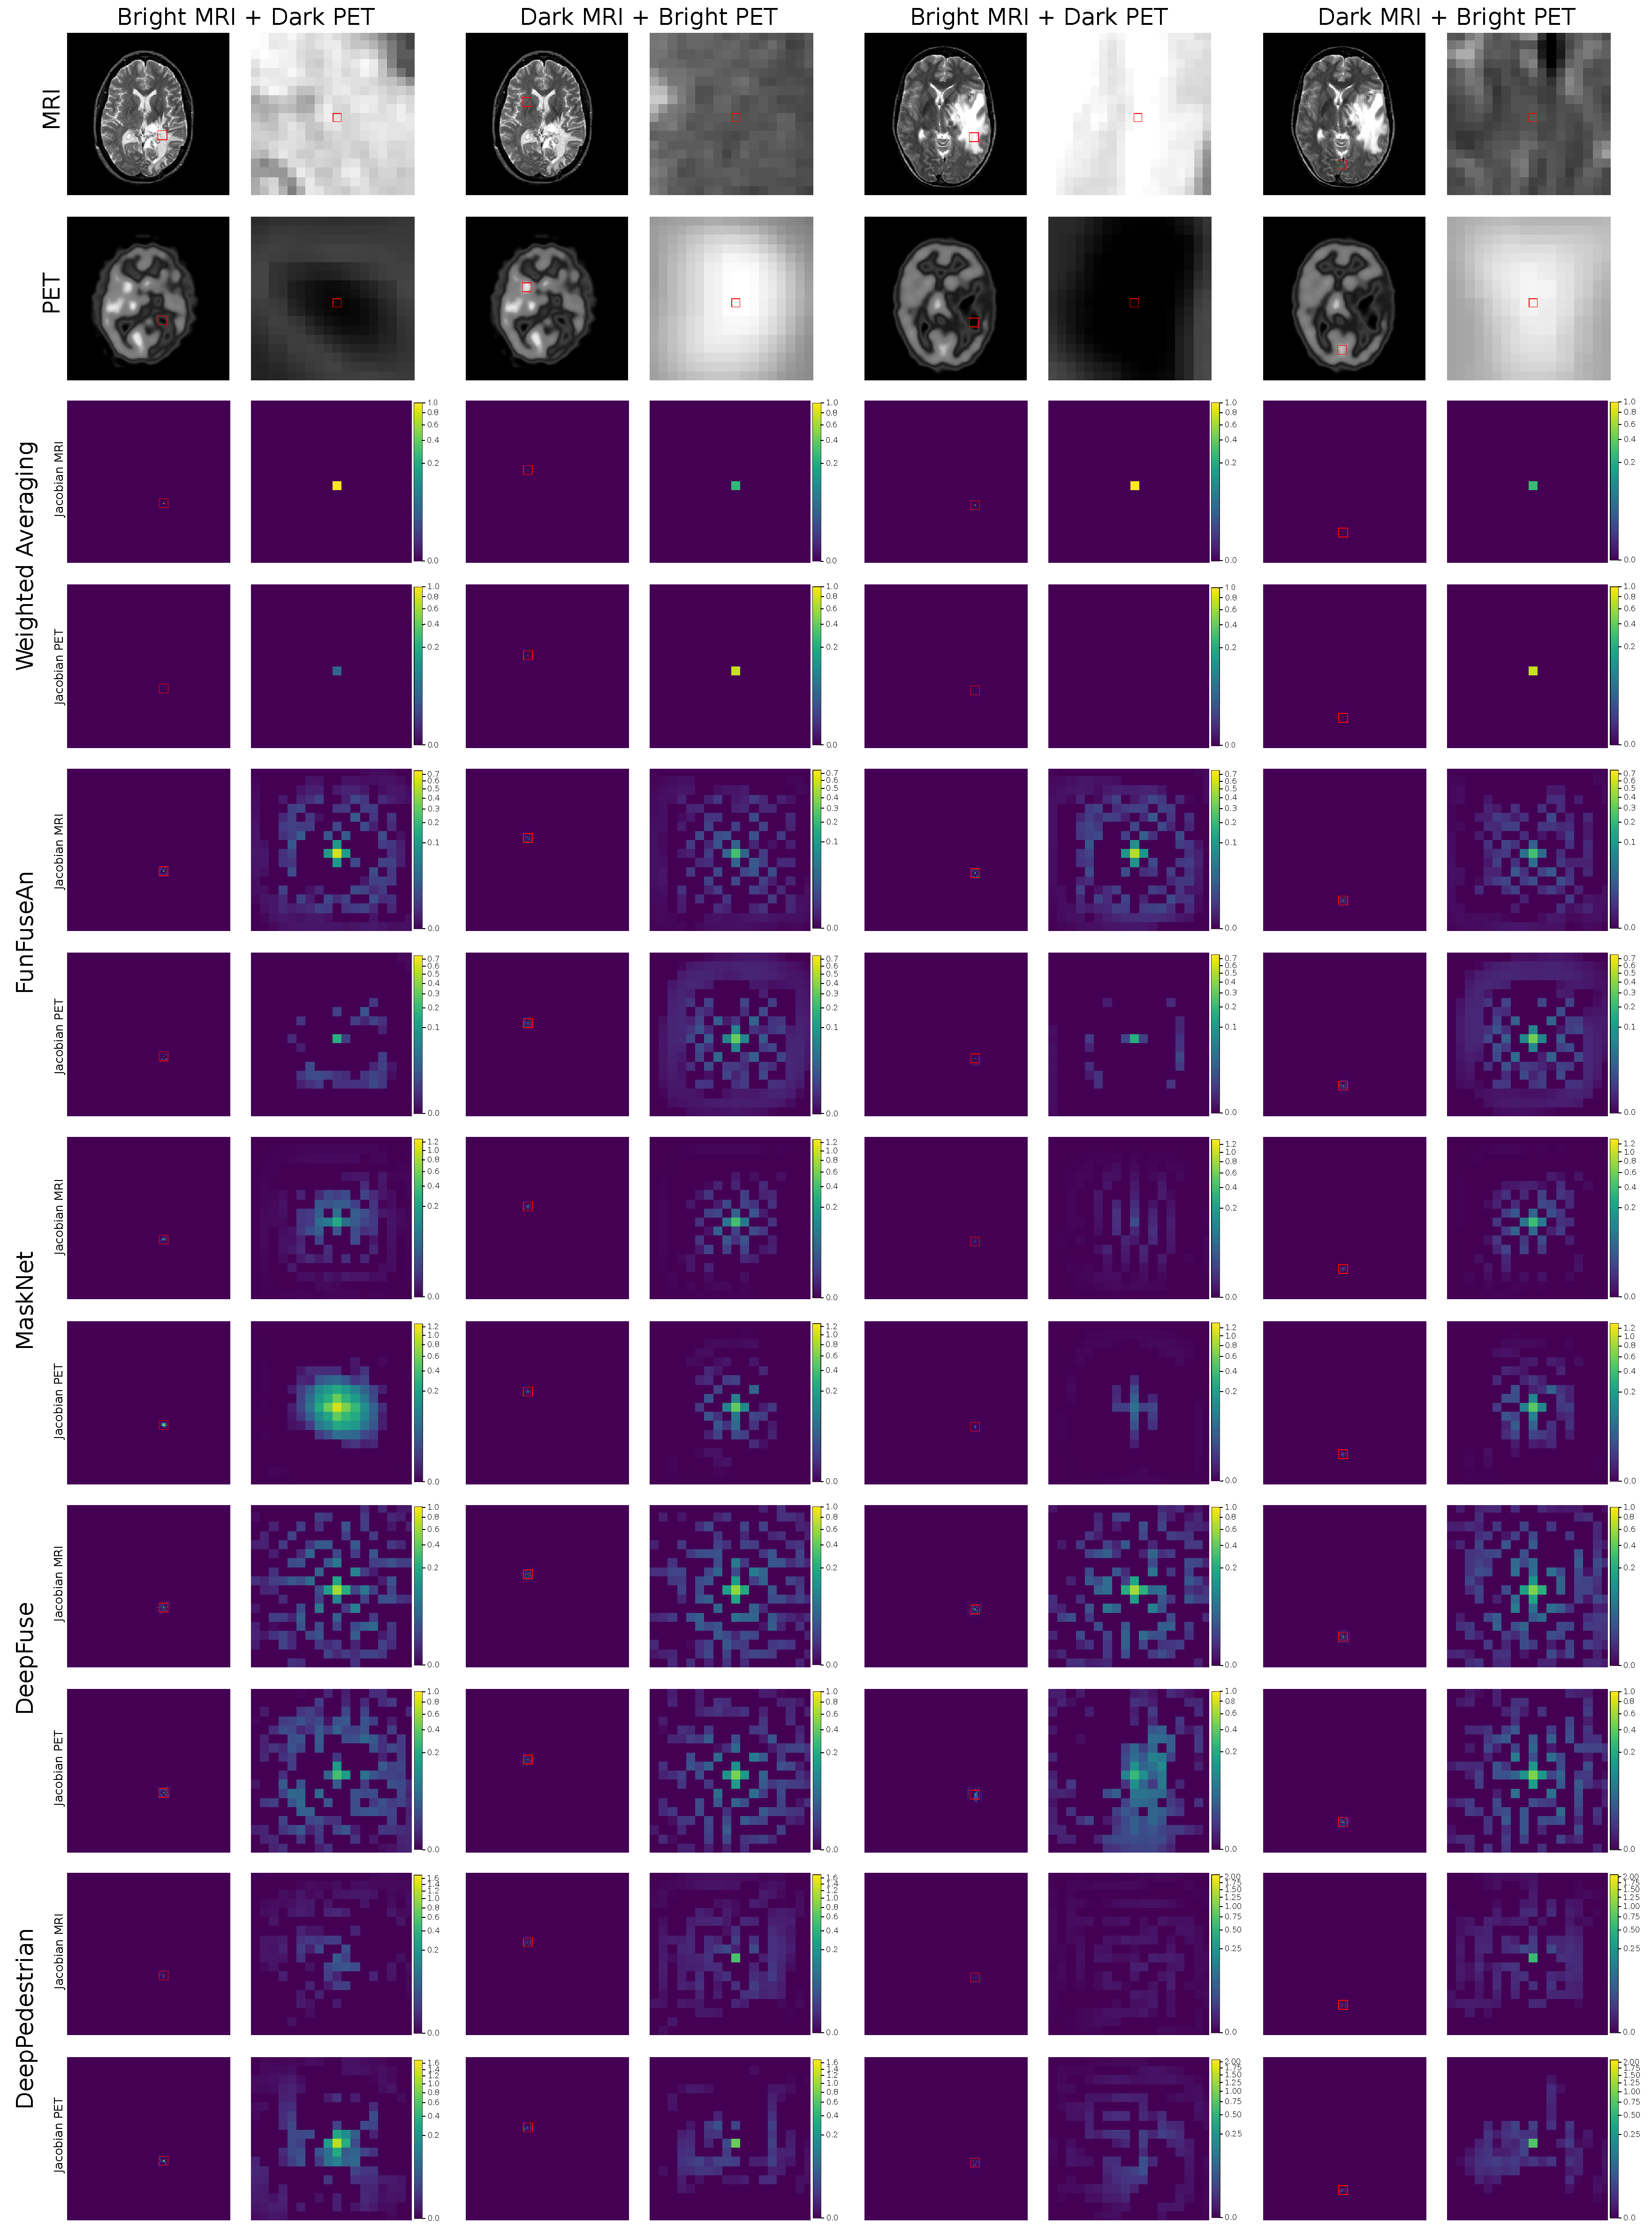

5.2. Clinical Test Examples

The clinical test examples were acquired from Harvard Whole Brain Atlas database [73] with the combination of MRI-T2 and PET/SPECT images from patients suffering from different types of glioma. The test examples were disjoint to the training dataset and the network has not seen such clinical pathology during its training. The first clinical MRI-PET image pair is shown in the first four columns of Figure 4. The scans are of a patient who was suffering from Anaplastic Astrocytoma, a rare and malignant brain lesion classified under the category of high-grade glioma. A lesion in the right and the left side of the brain is visible in the MRI image and has bright grayscale intensities. On the other hand, bright regions in the PET image convey normal blood flow while very dark regions suggest no blood flow in the necrotic tissues. In the second clinical MRI-PET image pair as shown in the last four columns in Figure 4, the patient had a long history of tobacco usage and was originally suffering from Metastatic Bronchogenic Carcinoma, which is a type of lung cancer. The patient began having headaches and the scans revealed brain metastases that occurred due to the spread of cancer cells present in the lungs to the brain resulting in the diagnosis of glioma. A lesion in the right side of the brain with bright features is visible in the MRI image while very dark PET features reveal no blood flow in the necrotic region.

• A fusion approach should assist clinicians in visualizing the extent of hyper dark PET regions resembling necrotic core with no blood flow being superimposed on the bright anatomical boundary of the whole tumor mass. This information is important for clinicians to estimate the extent up to which a tumor resection is required. For example, in the first and the fifth column of Figure 4, the principle pixel in this very dark PET region was chosen for visual analysis.

• A fusion approach should preserve the very bright PET features which convey high blood perfusion and normal metabolism in healthy brain tissues as it helps clinicians in visualizing the regions with high brain activity due to external stimuli at a particular time. For example, in the third and seventh column of Figure 4, the principal pixel in the bright PET region was chosen for visual analysis.

6.1. Fused Images

The fused images of the Weighted Averaging method as shown in the third row of Figure 4 gives very high weightage to the bright input intensities in the regions where intensities in the other modality are darker. Therefore, we can perceive a reproduction of features from relatively brighter regions of the MRI and PET images due to which Weighted Averaging method is unable to preserve the clinically important dark PET features related to the necrotic core but favorably preserves the bright PET features resembling healthy tissues. The fused images of the FunFuseAn as shown in the fourth row of Figure 4 are comparatively similar to the Weighted Averaging approach where it is not able to preserve the very dark PET features. However, the fused images from FunFuseAn look relatively dull compared to the fused images from Weighted Averaging since the FunFuseAn network mixes both MRI and PET features even though the boundary information about the necrotic region is lost.

The analysis of the fused images from MaskNet in the fifth row of Figure 4 shows a significant loss of anatomical edges from MRI such as the brain skull. However, contrary to Weighted Averaging and FunFuseAn, MaskNet preserved the PET features better in both the dark and bright regions resembling the necrotic core and healthy tissues, respectively. However, the dark PET features are slightly blurred due to changes in the overall brightness of the fused image. The fused image obtained from DeepFuse as shown in the sixth row of Figure 4 has an even higher shift in grayscale intensities due to which the method is unable to preserve the dark PET features even though the overall anatomical MRI structures are well preserved. The change in brightness can be explained by the fact that the L 2 M R I and L 2 P E T converged at higher loss values compared to other networks due to which the brightness component of SSIM was not properly optimized. Additionally, the architecture of DeepFuse network has been crafted for adding exposure to underexposed images by using the brightness component from each of the input image modalities and employ it to generate very bright fusion results. The fused image from DeepPedestrian as shown in the seventh row of Figure 4 clearly delineates the boundary of the necrotic core by preserving the very dark PET features, which is of high clinical significance for medical professionals. However, the anatomical edges from MRI are lost in the fused image which is also one of the main artifacts in the MaskNet network. Another important observation is that the bright PET features resembling healthy tissues appear to be not well preserved due to an overall brightness shift.

6.2. Guidance Images

In this section, we analyze the fusion methods with respect to its sensitivity to feature level changes in the input images by visualizing the Guidance MRI and Guidance PET images in Figure 5 and Guidance RGB images in Figure 6 for the two clinically relevant regions. We chose the first region as bright MRI with very dark PET features since it is the region that contains the necrotic core of glioma which clinicians are interested to operate for resection. The second region of interest has dark MRI with bright PET features resembling healthy tissues which is interesting for the visualization of high brain activity due to external stimuli. Ideally, a guidance MRI image should have low gradients meaning a fusion method should be less sensitive to changes in both dark and bright MRI regions.

6.2.5. Summary

The guidance images provided a static overview of the influence of input principle pixel on the fused principle pixel and assisted in visualizing which of the two modalities has higher influence in the clinical region of interest. Therefore, it provided new insights related to the stability of fusion networks in these regions which were not perceivable by looking at the fused images. The guidance images clearly show that MaskNet and DeepPedestrian networks performed very differently compared to other fusion methods. For the region with the dark PET features resembling necrotic core, all the methods except MaskNet and DeepPedestrian were sensitive to changes in the bright MRI intensities which is not suitable for a reliable analysis of the necrotic tumor boundary since the dark PET features might not be properly preserved in the fused image due to changes in the MRI features. Both MaskNet and DeepPedestrian preserved the dark PET features in the fused image and were quite stable to the changes in the MRI pixel intensities due to which both these methods are far more suitable for the clinical application than any other fusion methods. However, the guidance images do not reveal the influence of neighborhood pixels on the fused principle pixel which is important for estimating a better fusion approach between the two of these networks.

6.3. Jacobian Images

The jacobian images of the selected principle pixel is shown in Figure 7. The analysis of the jacobian images will help in understanding the influence of the neighborhood pixels located around the principle pixel in the clinically relevant regions of the input image. It will also assist in visually comparing the neighborhood influence of MRI pixels with PET pixels.

6.3.6. Summary

The analysis of jacobian images helped to visually compare the influence of the input neighborhood pixels from each of the input modalities on the fused principle pixel. It was observed that most of the fusion-based neural networks have a significant influence on neighborhood pixels. This visual analysis was not possible by only interpreting the guidance and fused images due to which jacobian images provide additional interpretation towards the suitability of a particular fusion method in a clinical setup. It was observed that Weighted Averaging has no neighborhood influence which is understandable by the fact that it is a per-pixel computation scheme. The MaskNet network, however, provides clinically favorable results as it has a high influence of neighborhood pixels within the necrotic core and very low influence from the pixels outside the necrotic core boundary.